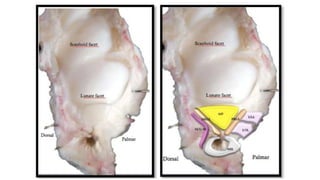

Central Disc

• Occupies 80 % of area

• Attaches to hyaline cartilage of sigmoid notch

Peripheral Disc

• Outer 20 % of area

• Vascular connective tissue along with

fibroblasts

• Good healing potential

• Blood supply

• Periphery portion : branch from ulnar artery and also from Ant. and Post. interosseous

arteries

• Central portion :nourished by synovial fluid